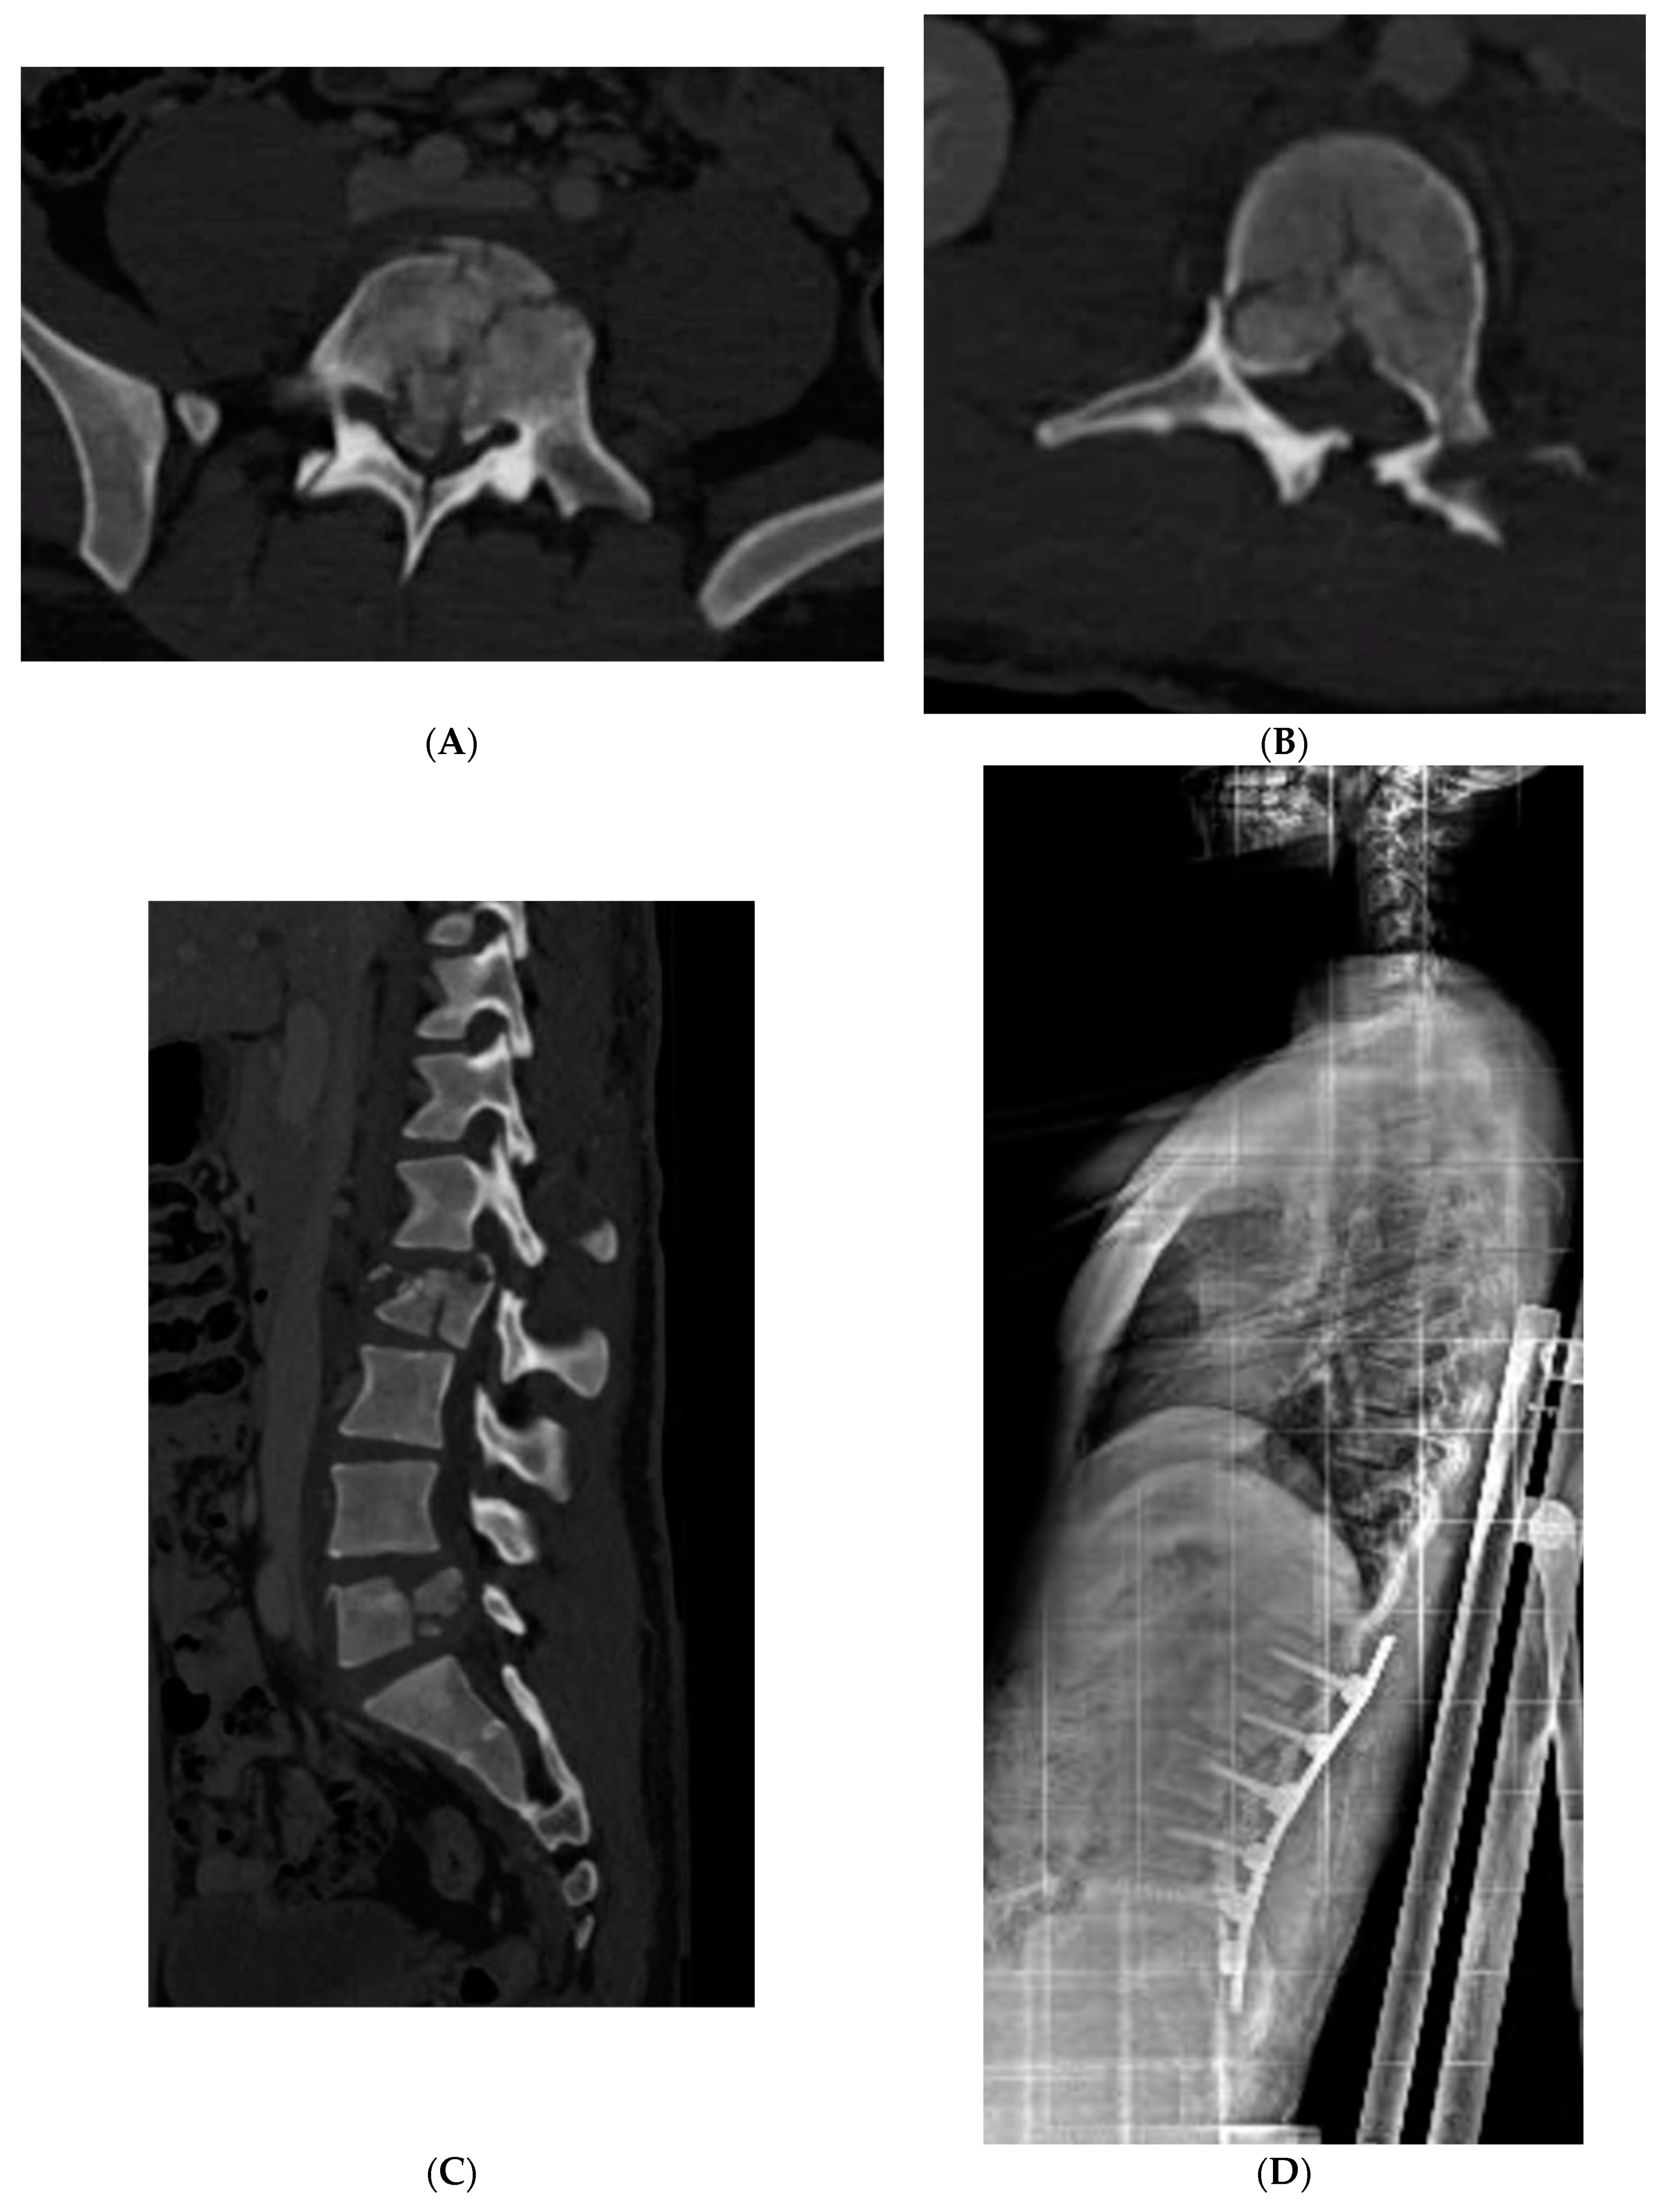

Only two patients with thoracolumbar A0 and A1 types of fractures (cases 4 and 5, Table 1) were conservatively treated with a rigid thoracolumbar orthosis for 3 months with good compliance and results. Percutaneous pedicle fixation was applied in seven patients with an indirect decompression and to restore a better sagittal balance (images case 6 and 10, Table 1). Only in two cases there were a neurological impairment. In both cases an open spinal decompression and posterior spinal fusion was performed open. All surgically treated patients used a soft spine orthosis for 1 month to facilitate early mobilization and to reduce muscular pain.

Figure 2. Case 10 (Table 1), (A) preoperative axial CT scan of L5, (B) preoperative axial CT scan of L2, (C) preoperative sagittal CT scan of lumbar spine, (D) post operative Xray lateral view in sitting position.